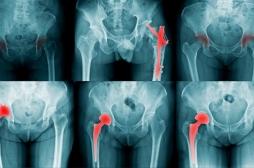

fracture